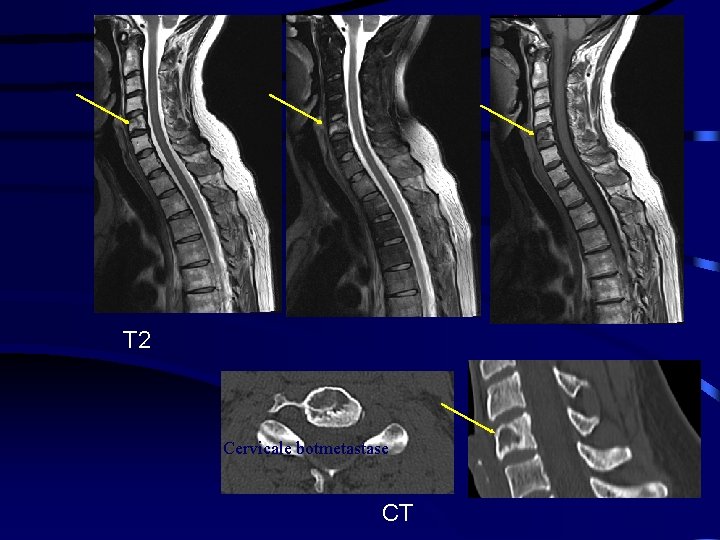

T 2 Cervicale botmetastase CT